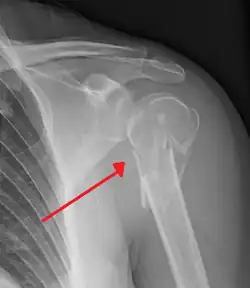

Fracture of the proximal humerus -

The head (caput humeri) is nearly hemispherical in form. It is directed upward, medialward, and a little backward, and articulates with the glenoid cavity of the scapula to form the glenohumeral joint (shoulder joint). The circumference of its articular surface is slightly constricted and is termed the anatomical neck, in contradistinction to a constriction below the tubercles called the surgical neck which is frequently the seat of fracture. Fracture of the anatomical neck rarely occurs.[2] The diameter of the humeral head is generally larger in men than in women.

Surgical neck

The surgical neck is a narrow area distal to the tubercles that is a common site of fracture. It makes contact with the axillary nerve and the posterior humeral circumflex artery.